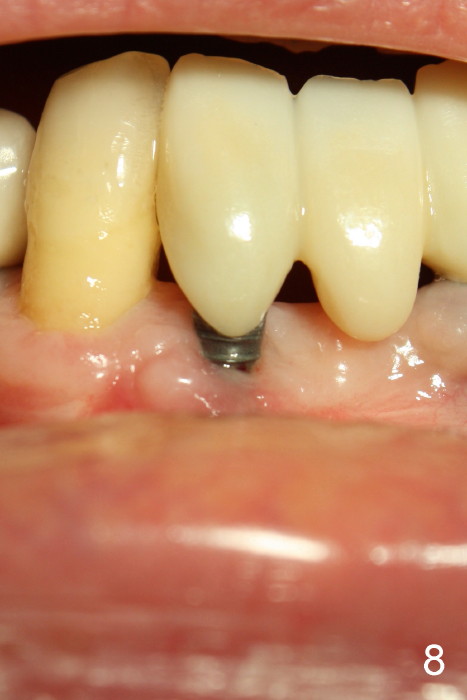

Fig.5 is taken following local anesthesia to show the exposed mesh, 22 days post placement. When the latter is removed, the exposed threads appear to be less (Fig.6, as compared to Fig.2). There is healthy granulation tissue growth apically (*). The patient is asymptomatic 1 month post mesh removal; there is no tenderness around exposed threads (Fig.7). Connective tissue graft is planned to cover the exposed threads through tunnel technique. Thread exposure appears less 3 months post mesh removal (Fig.8). There is infection when the region is not kept clean (Fig.9 (2.5 years post mesh removal)). The other 1-piece implant should have minor implant exposure (<). It appears that there is no thread exposure associated with the immediate implant at #28. Using smaller 1-piece implants (2.5 or 2.0 vs. 3 mm) with flap surgery should be able to prevent the complication. The 72-year-old phobic patient declines any further treatment. Two years later, she agrees to have treatment because of repeated infection (Fig.10). Impression has been taken for stent. After sectioning FPD and removing the infected implant (Tatum), a smaller implant will be placed in between the implants. If her vein is not too small, blood will be drawn for PRF.